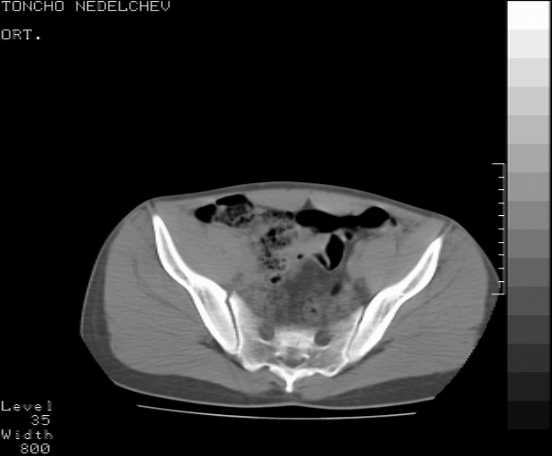

Here are some more axial images. What is your opinion as for the timing of the operative treatment?